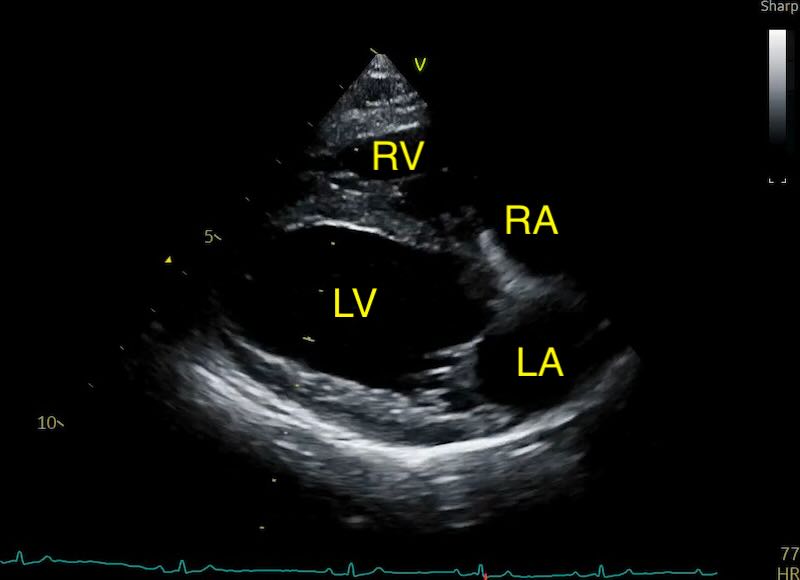

Veterinary cardiology is increasingly moving toward the Left Atrial anteroposterior Dimension (LAD). Measured from the right parasternal long-axis view, the ‘4 Chamber’ view, this metric is often more repeatable, easier to acquire in a struggling patient, and provides a clearer picture of the atrium’s true expansion.

The LAD is measured using the Right Parasternal Long-Axis 4-Chamber view (RPLA4Ch). This is often called the “heart homepage” because it allows for a comprehensive subjective and objective assessment of all four chambers simultaneously. See our article on echo views here.